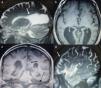

Imágenes de RMC del caso 2. a) Corte sagital en T2. Se ve la gran diferencia en el tamaño del ventrículo lateral, normal en la prolongación frontal y muy agrandado (a partir de la flecha) en la región occipital. b) Corte axial en T1. Se observa el tercer ventrículo con la flecha señalando la rodilla adelgazada del cuerpo calloso. c) Corte coronal en T1. Se ve el rodete del cuerpo calloso (flecha) cruzando la línea media a nivel de la fosa posterior (flecha punteada sobre la tienda del cerebelo). d) Corte sagital en T2. Se observan los surcos corticales frontales y occipitales que, a diferencia del caso 1, tienen similar ensanchamiento.